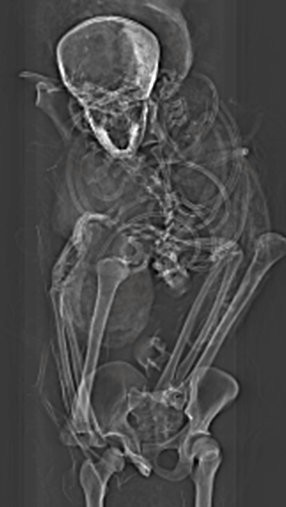

一开始不少专家都认为塞克嫩拉可能是在宫殿睡觉时被刺客杀害,但始终未有更详尽的证据,让学界对他的死因争论不休。不过开罗大学(Cairo University)放射学教授萨利姆(Sahar Saleem)与研究团队利用电脑断层扫描,发现防腐剂巧妙地掩盖头骨右侧的其他伤口,加起来总共有5个大大小小的伤口,包括额头上一道横切伤、右眉上方、左眼下方及左耳下都有伤痕,右眼窝骨头则被钝器砸碎,身体则没有受伤。

研究中也分析5种不同的西克索人武器,并与塞克嫩拉的伤口进行匹配。萨利姆表示,武器中包括包括战斧、长矛和3种不同的匕首,塞克嫩拉很可能是在仪式中被处决,因为通常一般执行处决时,刽子手只会从同一角度执行,鲜少以不同角度、不同武器进行5次攻击,且考量到木乃伊保存状况较差,显见防腐过程处理匆促,且并非在皇家木乃伊工作坊完成。

萨利姆说,过去历史并未记载塞克嫩拉曾参与和西克索人的战争,而这项发现重写了古埃及历史上的重要章节,更让人们得知法老曾在于前线作战,据电脑断层分析结果显示,塞克嫩拉死时享年40岁,“他的死并没有白费,促使他的儿子们完成一统埃及的遗愿,并建立起全新的王国。”